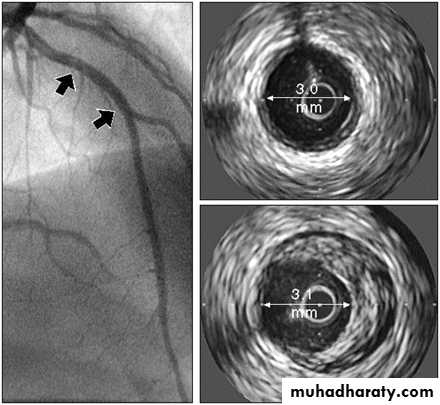

Intravascular Ultrasound (IVUS) Showing Atheromatous Plaque

Reproduced from Circulation 2001;103:604–616, with permission from Lippincott Williams & Wilkins.Angiogram

IVUSatheroma

normal vesselCoronary Angiographyof Stenotic Coronary Artery

6

Arrow indicates atherosclerosis (stenosis) of the coronary artery